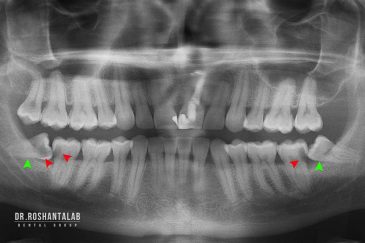

🔸جراحی پیشرفته نظیر سینوس لیفت

از عصب کشی و درمان ریشه دندان گرفته تا جراحی لثه و کشیدن دندان، تمامی مراحل توسط متخصص ترمیم دندان مدیریت میشود. ارائه باکیفیتترین خدمات ترمیم دندان برای سلامتی شماست.کاشت ایمپلنت فوری دندان